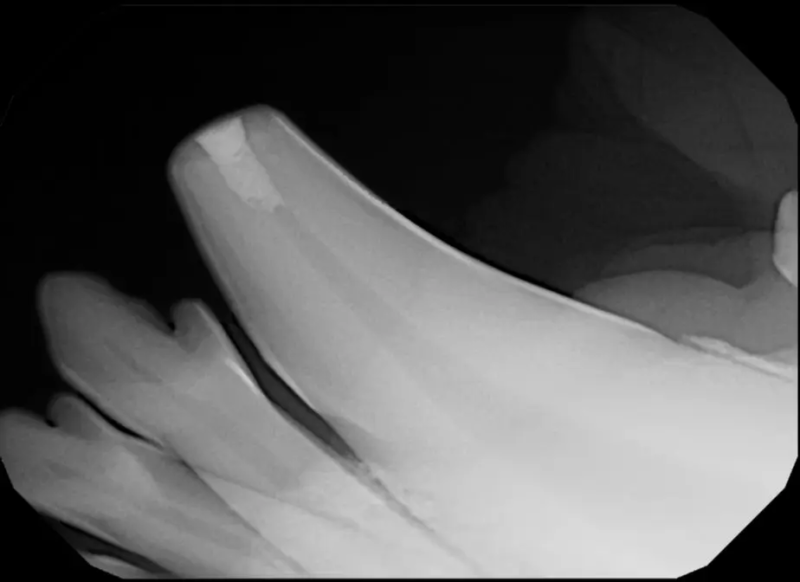

Root Canal Therapy

Root canal therapy is an excellent option for saving important teeth that have been fractured or are determined to be non-vital. The procedure is performed exactly as it would be for a human, except your pet will be dreaming peacefully under anesthesia. In many cases, root canal therapy is much easier on your pet than extraction, and preserves the structure of the tooth. It is important to have the root canal x-rayed periodically to monitor for any problems.

Surgical Extraction of Diseased Teeth

Periodontal disease is extremely common in dogs and cats. Over 80% of dogs and cats over two years of age have some degree of periodontal disease. Periodontal disease is best prevented by yearly professional dental cleanings starting at two years of age and at home brushing at least three times weekly. Brushing should begin at a very early age to allow your new pet to get used to regular brushing. In severe cases of infection or periodontal disease, the teeth may need to be surgically extracted. Extractions should always involve x-rays of the tooth first, as many teeth have multiple roots or may be diseased below where the eye can see. Extracting larger teeth in animals requires oral surgery, equivalent to removing wisdom teeth in people. It is vital that all of the tooth and roots be removed for the periodontal infection to resolve. In cases of important teeth with mild to moderate periodontal disease, multiple periodontal treatments can be offered to help save these teeth.